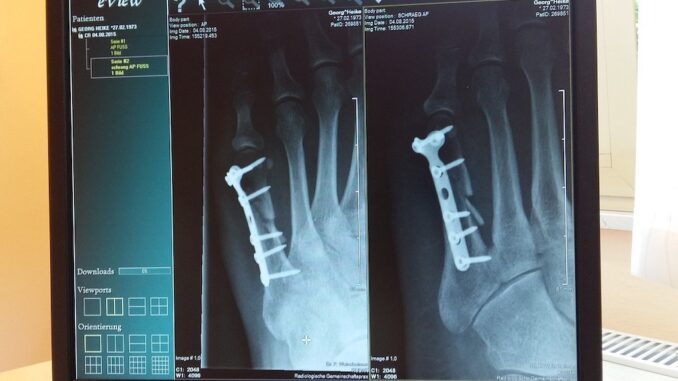

Weltweit leiden Millionen von Menschen an Osteoporose. Es handelt sich um eine Krankheit, die die Knochen betrifft. Das Gefährliche daran: Sie beginnt oft schleichend und verursacht in vielen Fällen keine Schmerzen oder Beschwerden, bis es jedoch zu einem Knochenbruch kommt. Aus diesem Grund ist es umso wichtiger, frühzeitig die Weichen für eine gute Knochengesundheit zu stellen.

Bild: Heike Georg via Pixabay